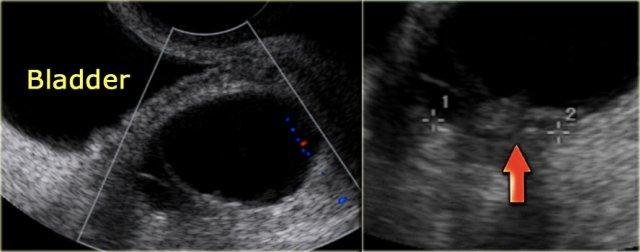

Các hình ảnh siêu âm qua ngã âm đạo cho thấy một nang buồng trứng phức tạp nhỏ với mạch máu thành nang trên phân tích Doppler năng lượng.

Hình ảnh Doppler vòng tròn đặc trưng này được gọi là dấu hiệu ‘vòng lửa’ (ring of fire).

Lưu ý, có hiện tượng xuyên âm tốt và không có mạch máu bên trong, phù hợp với nang hoàng thể đang thoái triển một phần.

Một trường hợp khác với hình ảnh điển hình của dấu hiệu ‘vòng lửa’ trên siêu âm.